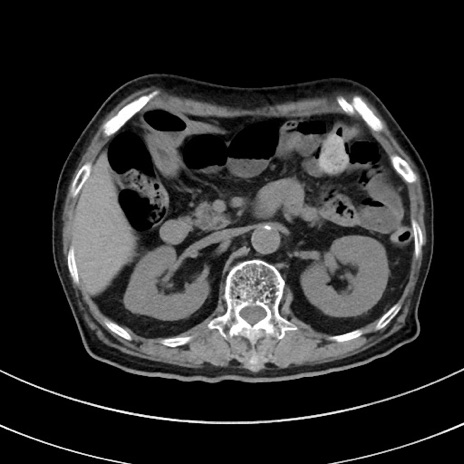

症例33(横断像)

【症例】70歳代 女性

【主訴】心窩部痛

【現病歴】延髄病変の精査・加療にて神経内科入院中。本日より心窩部痛あり。

【既往歴】虫垂炎

【身体所見】右下腹部を中心に圧痛と反跳痛あり。

【データ】WBC 10900、CRP 0.02